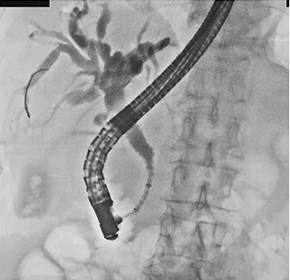

症例1は、膵頭部がんに対し化学療法を施行した症例である。術前に金属ステントを留置したが、黄疸が悪化したため、Duckbill型逆流防止弁付き金属ステントに変更した。Duckbill型逆流防止弁付き金属ステントは、内視鏡下ではマーカーが見えにくいため、透視下で十二指腸下行脚部を確認しつつ問題なく留置することができた(図5)。

図5 症例1:膵頭部がん(62歳、女性)

Duckbill留置

パルスレート7.5fps、線量モード:Normal